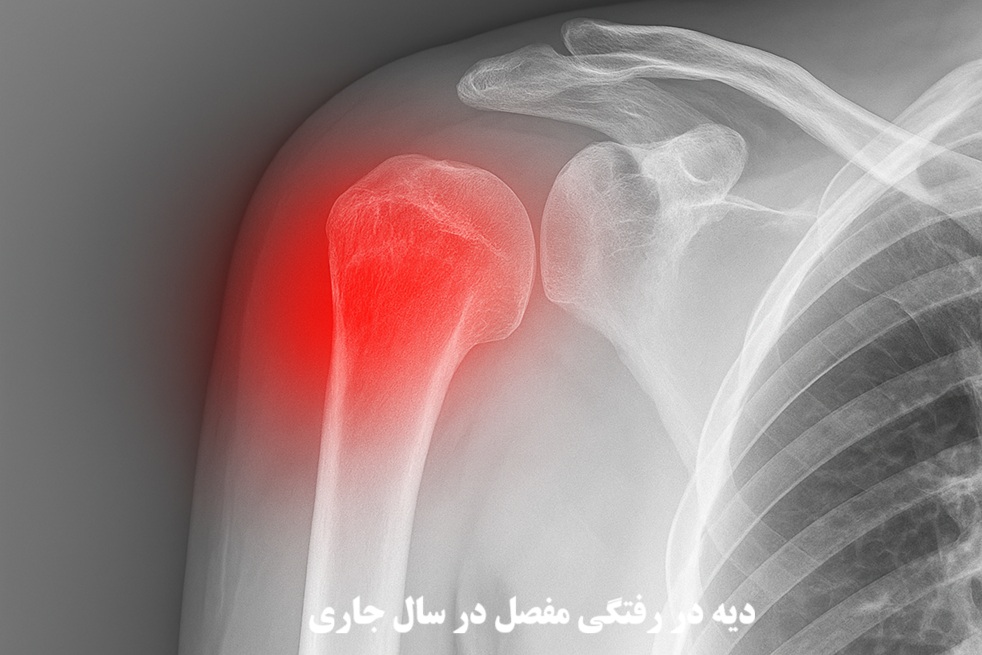

در نظام حقوقی ایران، تعیین دقیق دیه برای شکستگی استخوانهای بدن، نقشی حیاتی در احقاق حقوق آسیبدیدگان دارد. دو ناحیه